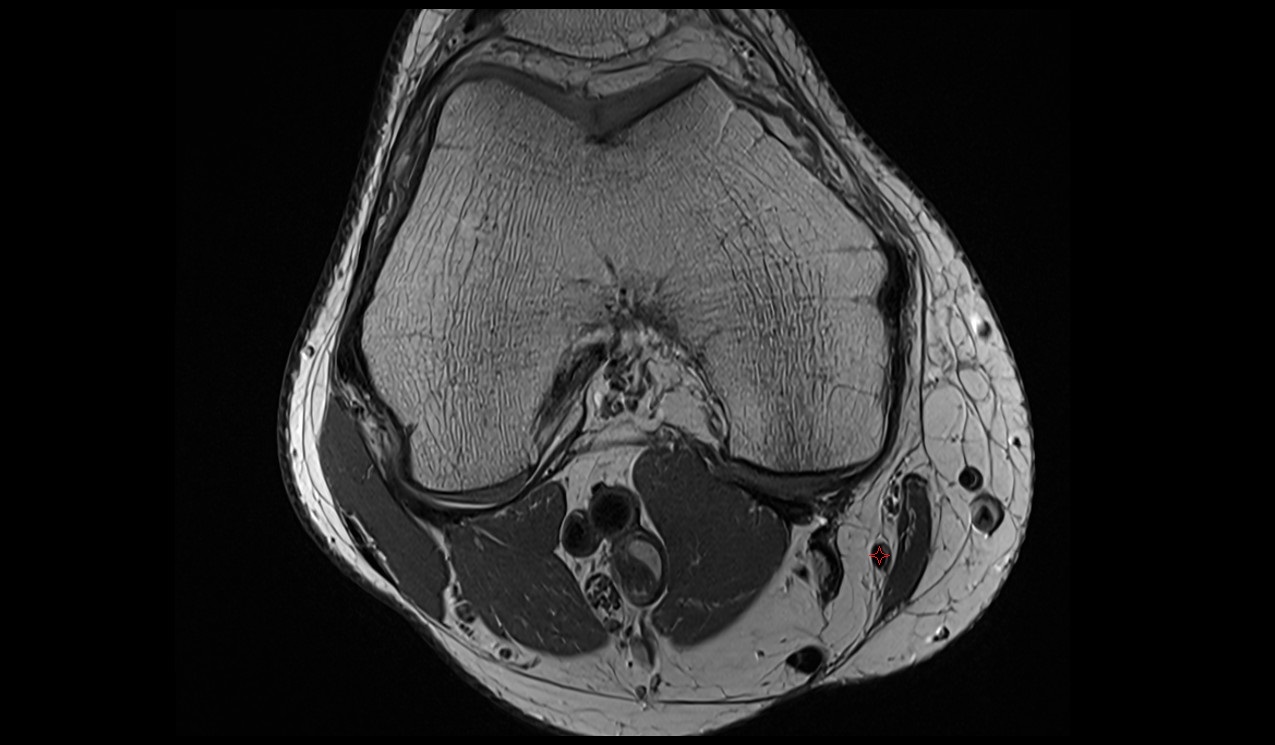

- Knee Joint